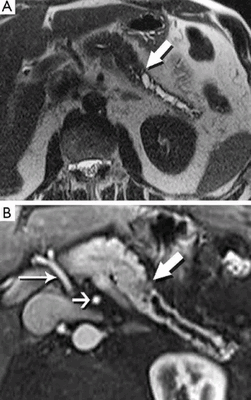

МРТ с контрастом, коронарная плоскость: протоковая карцинома головки поджелудочной железы, прорастание в брыжейку тонкой кишки (стрелки)